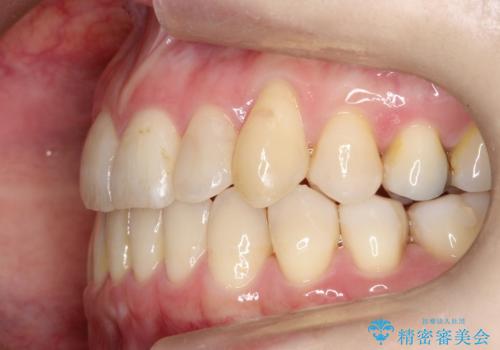

- 左上の八重歯の改善を希望され来院された患者様です。

見た目、嚙み合わせ及び、治療期間や施術内容に大変ご満足いただきました。